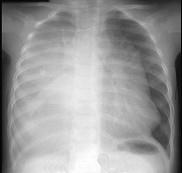

问题 12岁,女,咳嗽、咯血1个月,咳出毛发、钙化物,请结合图片,选择最可能的诊断 ( )

选项 A.肺间质纤维化 B.肺曲菌病 C.肺结核 D.畸胎瘤 E.肺癌

答案 D